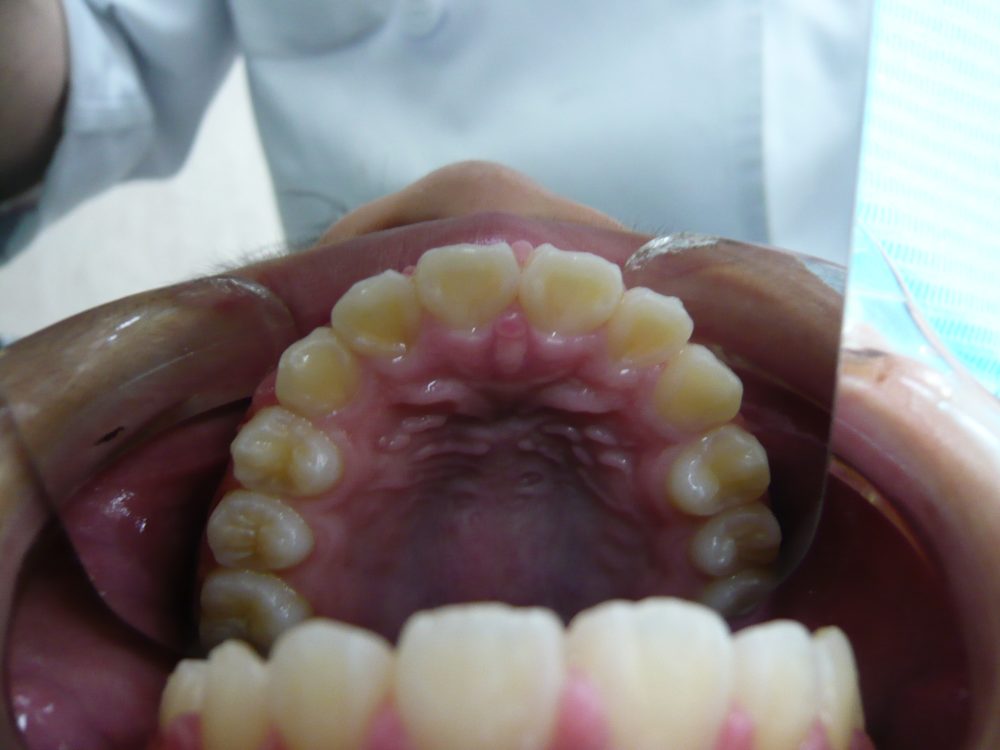

右上の犬歯が八重歯となっています。

これくらいの乱れなら、半年足らずできれいにすることができました。